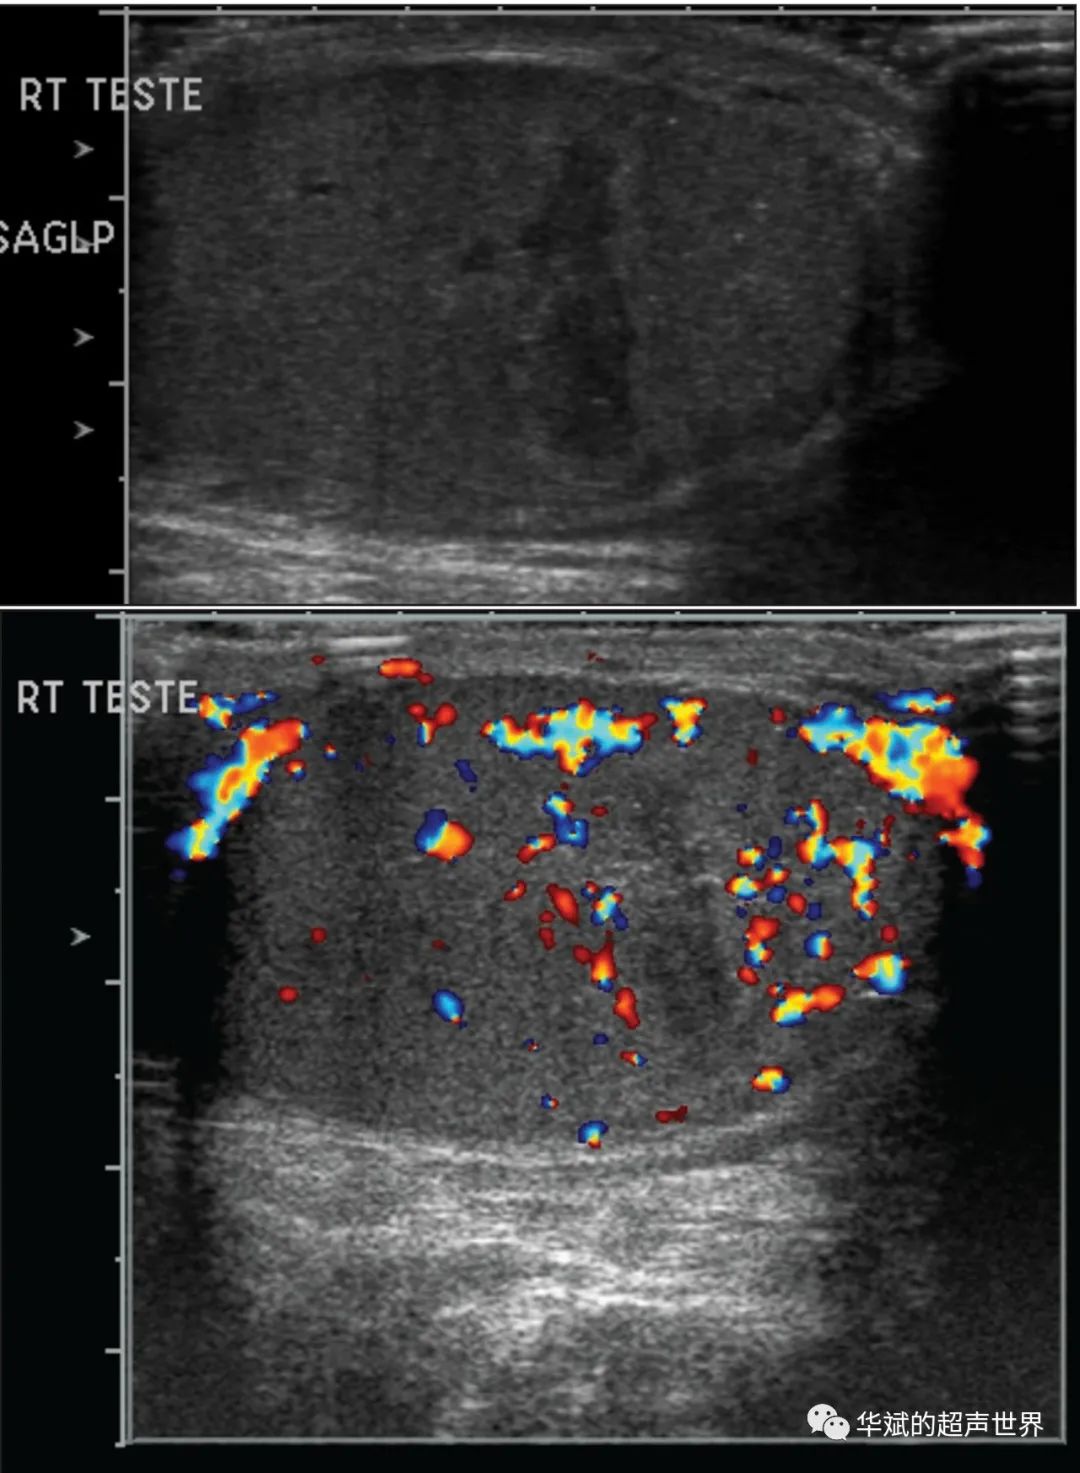

节段性睾丸梗塞 令人尴尬的 楔形 华斌的超声世界 二十次幂